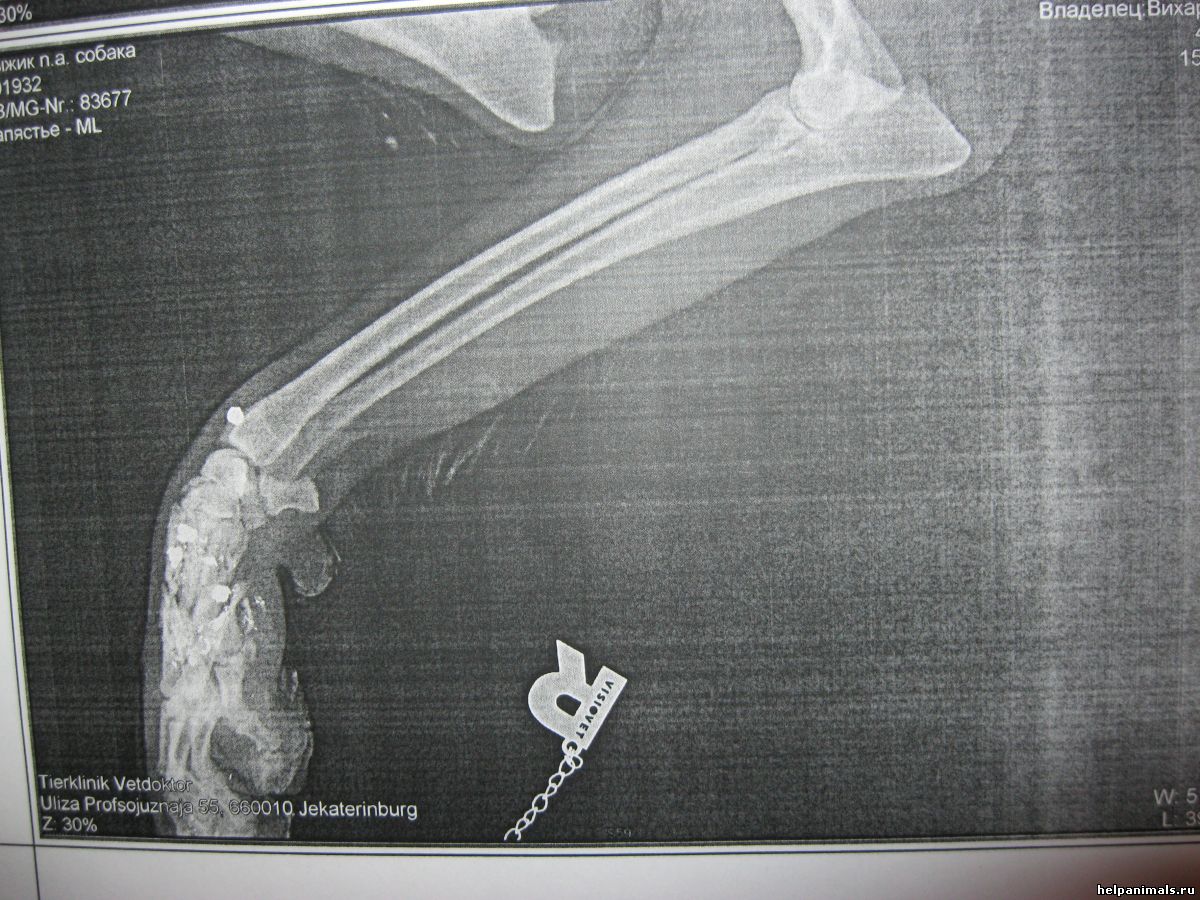

Сама наблюдала. Молодчина. По снимкам лап Тебеньков В.В. сказал, что в передней идет процесс срастания, вернее образовывается нарост. А вот по задней-пока все проблематично. По снимкам до сих пор (прошло как раз 2месяца) образования чего-либо нет. Но чтобы все-таки дождаться результата надо быть в лангете 5мес.со дня получения травмы. Может и случится чудо. Все очень не предсказуемо....Там и осколки костей и куски металла, и ожог, и мягкие ткани разрушены.... Жить так ему еще до середины ноября и если вдруг ничего там не нарастет, то делать операцию: пластинами с двух сторон зафиксировать кости и это будет заменять сустав, лапа будет только как опорная, к большому сожалению. Оплачена передержка с 13.08 до 22.08 3500руб Денег для Рыжика уже нет. платить за передержку сейчас по 350р/сутки+ очень нужны пеленки Когда вылечим лапы, постараюсь найти место чтоб самой справиться с оплатой. Очень прошу всех, кому жалко пострадавшего Рыжика, помогите пожалуйста собрать деньги на оплату передержки. Будем очень всем благодарны. Только что перевела 500 рублей на голодный номер Билайн